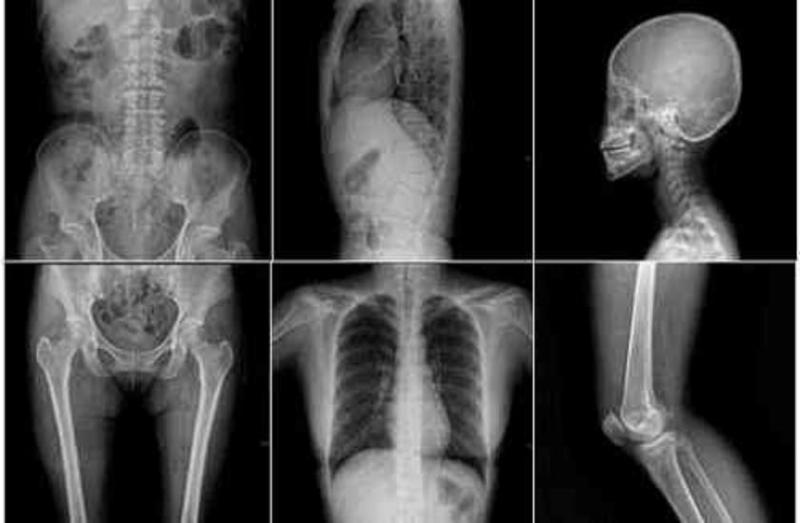

आपको बता दें कि दुनिया में एक ऐसी लड़की है जो कि अपनी आंखों से ही एक्स-रे का काम कर सकती है। इस लड़की का नाम नताशा डेमकिना है और ये रूस की रहने वाली है।

इस लड़की को दुनिया जीती-जागती एक्स-रे मशीन के नाम से जानती है। जी, हां नताशा में एक ऐसी अद्भुत शक्ति है जिसके बारे में जो भी सुनता है वो ही हैरान हो जाता है और तो और वैज्ञानिक भी इस रहस्य का उजागर आज तक नहीं कर पाएं है।

नताशा की आंखे एक्स-रे मशीन की तरह से काम करती है, जो किसी भी इंसान के अंदर के अंगों को देखकर उसकी बीमारी के बारे में आसानी से पता लगा लेती है।

नताशा ने ऐसा कई बार किया है और बाद में जब सच में एक्स-रे मशीन से मरीज की जांच की गई तो रिपोर्ट में वही था जैसा कि नताशा ने बताया था। डॉक्टर्स ऐसा होते देख अचरज में पड़ गए।

आज तक नताशा ने अपनी आंखों से देखकर जो कुछ भी बताया है वो कभी गलत नहीं हुआ है। हालांकि, शरीर के अंदर की खराबी को देखने और उसको समझने में नताशा को कुछ समय ज़रूर लगता है लेकिन वो किसी भी बीमारी को बिल्कुल सही पहचान लेती है।